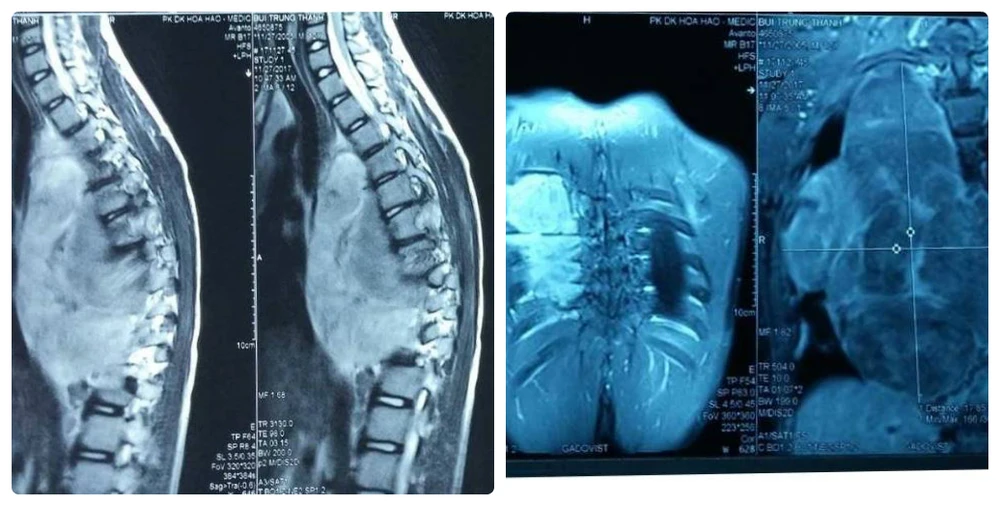

Phim chụp X-Quang cho thấy khối bướu khủng trong lồng ngực lan sang ống sống gây biến dạng cột sống.

Tại BV Nhi đồng 1, qua các xét nghiệm hình ảnh, bé T. được chẩn đoán có khối bướu khủng chèn ép chiếm toàn bộ mặt phổi bên trái, kích thước 18 x 13,5 x 9 cm và phát triển lan đốt sống, chèn ép lên tủy.

Đây là nguyên nhân khiến bé vẹo cột sống, tê yếu hai chân dưới. Sau khi nhập viện, tình hình sức khỏe bé giảm sút nhanh khi sức cơ chân từ 4/5 giảm xuống còn 1/5, liệt cứng hai chân, tiêu tiểu mất cảm giác.

ThS-BS Đinh Việt Hưng, khoa Ngoại tổng hợp, nhận định: “Đây là trường hợp khó khăn điều trị, khối bướu đã lan sang ống sống, nơi chứa tủy sống và các rễ thần kinh khiến bé yếu dần, liệt dần. Nếu không điều trị kịp thời, bé sẽ có nguy cơ liệt hoàn toàn và không hồi phục dù có giải quyết được bệnh. Do đó, ca phẫu thuật ưu tiên giải áp cho tủy sống trước, làm giảm tổn thương cho tủy”.